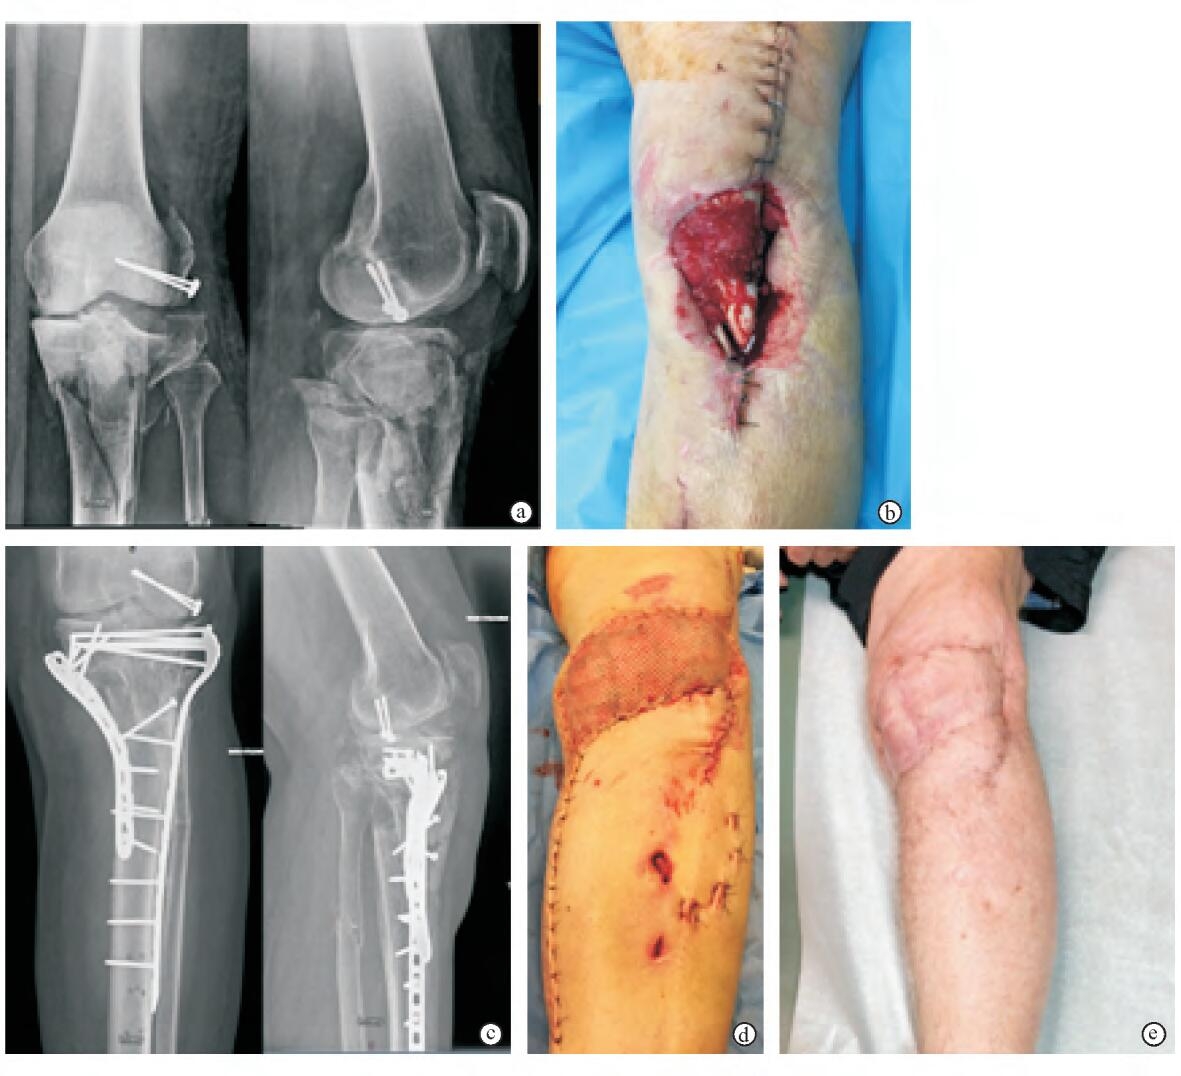

病例3——腓肠肌内侧头肌瓣转移治疗膝关节骨折合并软组织缺损

腓肠肌内侧头肌瓣治疗膝关节开放性骨折伴皮肤软组织缺损

a.急诊处理后X线片示股骨远端外侧髁骨折予拉力螺钉固定,胫骨平台粉碎性骨折和腓骨骨折跨关节外支架固定

b.拆除外固定支架清创后见胫骨近端软组织缺损,髌韧带裸露

c.术后X线片显示股骨外髁、胫骨平台复位内固定情况

d.术后大体照片显示创面关闭情况,转移的腓肠肌表面网状植皮

e.术后10个月膝部皮肤软组织愈合

患者股骨远端和胫骨平台开放性骨折,急诊行清创术、股骨远端有限内固定和跨关节外支架固定。术后2周拆除外固定支架,再次清创后患者遗留膝关节前下方皮肤软组织缺损及髌韧带外露。

对该患者给予如下处理:首先,在股骨外髁及胫骨平台处切开复位内固定,然后用腓肠肌内侧头肌瓣转移覆盖膝关节前下方伤口,并在肌瓣表面行网状植皮。3周后植皮存活,伤口顺利愈合。术后10个月复查,骨折愈合,患者对膝关节功能满意。